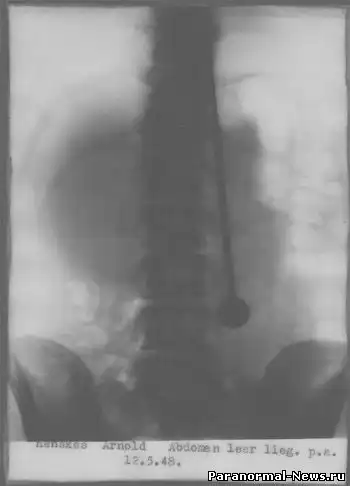

Конечно, Дажо проверяли врачи, причем не раз. В конце мая 1947 года он продемонстрировал свои таланты в Цюрихском кантональном госпитале. Как обычно, Ми-рин разделся до талии. Когда ассистент пронзил рапирой сердце, легкие и почки, он, как обычно, не почувствовал боли и не проронил ни капли крови. Чтобы исключить возможность гипноза, было решено сделать рентген, но медики не знали, как доставить его до рентгеновского кабинета — ведь носилки не приспособлены к транспортировке людей, пронзенных рапирами. Дажо успокоил их, сказав, что сам дойдет куда нужно — с рапирой естественно. Снимки исключили всякие сомнения: клинок прошел через несколько жизненно важных органов,но не причинил никаких повреждений.

Рентген исключил всякие сомнения: клинок прошел через несколько жизненно важных органов, но не причинил никаких повреждений.